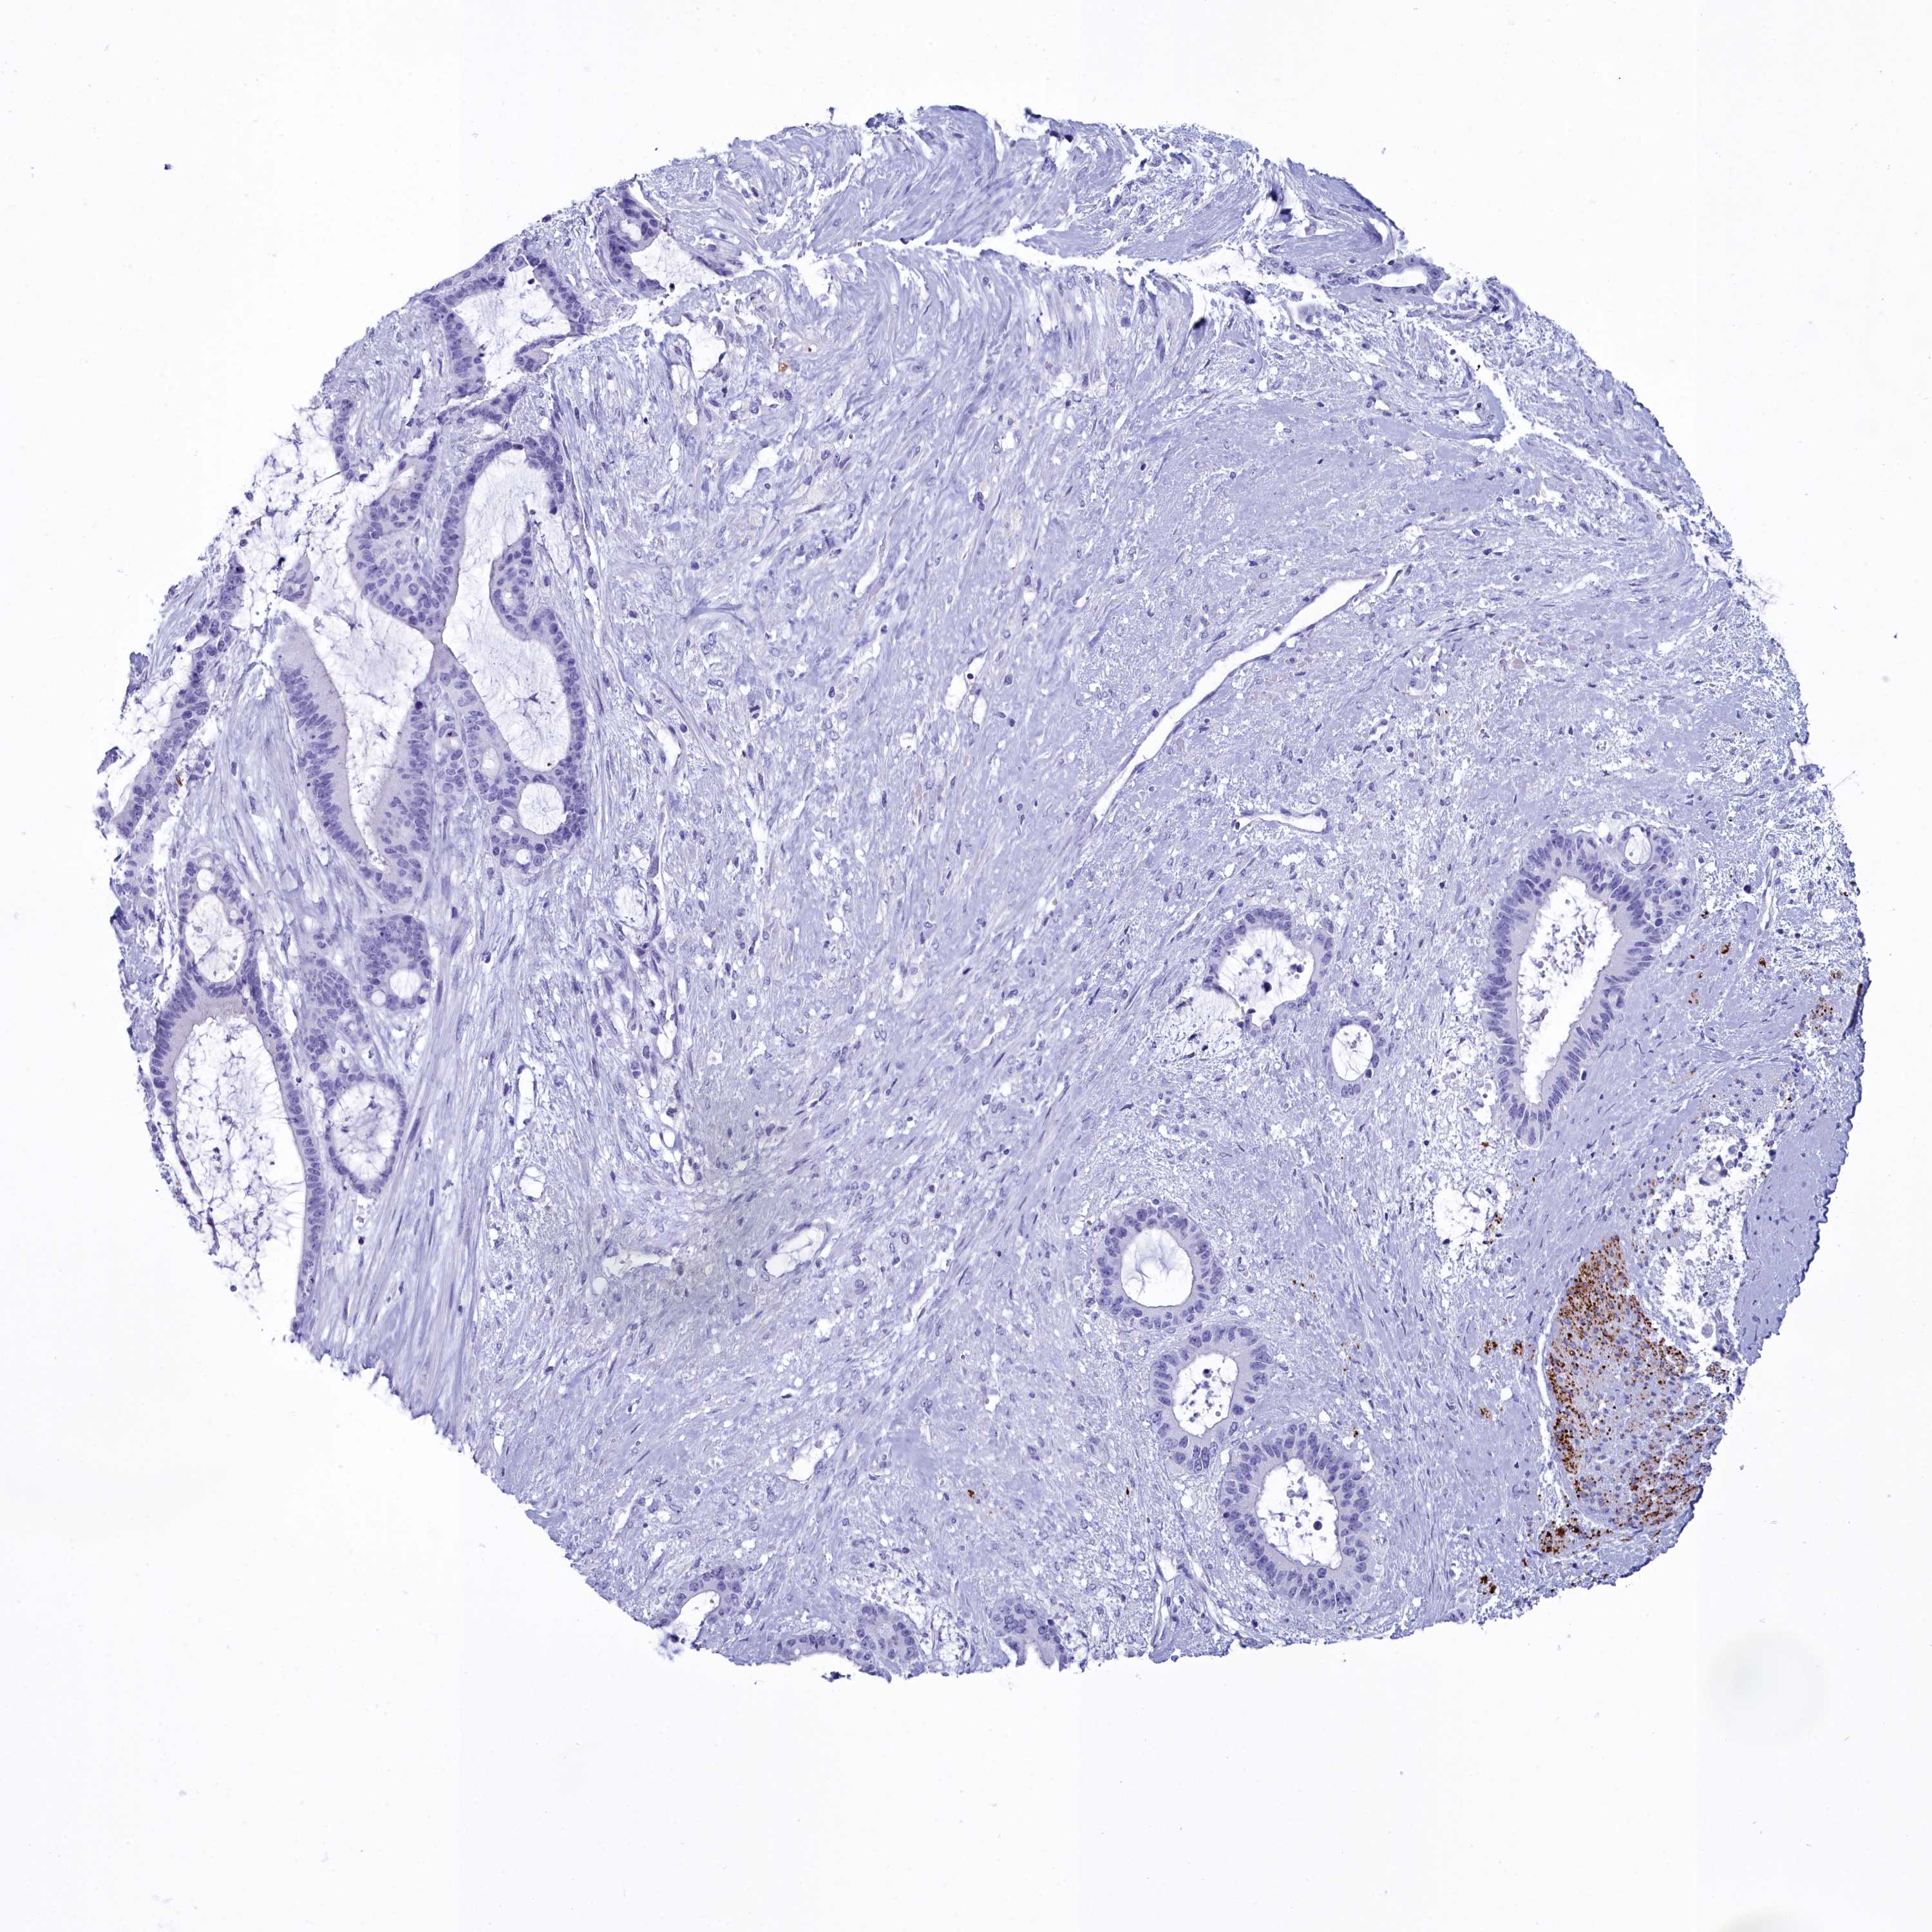

LIVER CANCER - Protein expressioni

A mouse-over function shows sample information and annotation data. Click on an image to view it in a full screen mode. Samples can be filtered based on level of antibody staining by selecting one or several of the following categories: high, medium, low and not detected. The assay and annotation is described here.

Note that samples used for immunohistochemistry by the Human Protein Atlas do not correspond to samples in the TCGA dataset.

Antibody stainingi

Antibody staining in the annotated cell types in the current human tissue is reported as not detected, low, medium, or high, based on conventional immunohistochemistry profiling in selected tissues. This score is based on the combination of the staining intensity and fraction of stained cells.

Each image is clickable and will lead to virtual microscopy that enables deeper exploration of all samples and also displays staining intensity scores, fraction scores and subcellular localization as well as patient and tissue information for each sample.

Antibody HPA039061

Antibody HPA039062

Antibody CAB015442

Antibody CAB022600

Cholangiocarcinoma

Carcinoma, Hepatocellular, NOS